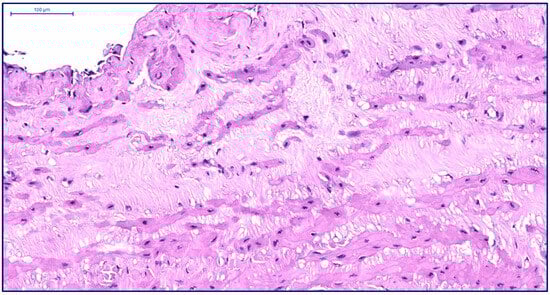

More pronounced structural alterations appear in the great saphenous vein of middle-aged and elderly individuals under normal conditions. Age-related changes manifest as uneven wall thickness and structural heterogeneity. Areas with thinner walls show reduced proportions of longitudinal and circular smooth muscle layers, while thicker regions contain these layers at maximal density (Figure 2 and Figure 3). The circular smooth muscle bundles become increasingly separated by connective tissue, creating a disorganized appearance.

Figure 2. Fragment of the great saphenous vein in individuals of the second age group. Hematoxylin and eosin staining. Magnification × 100. Segment of the vein with minimal and maximal wall thickness.

Figure 3. Fragment of the great saphenous vein in individuals of the second age group. Hematoxylin and eosin staining. Magnification × 200. Clearly defined layer of longitudinally oriented smooth muscle cells of the middle layer.